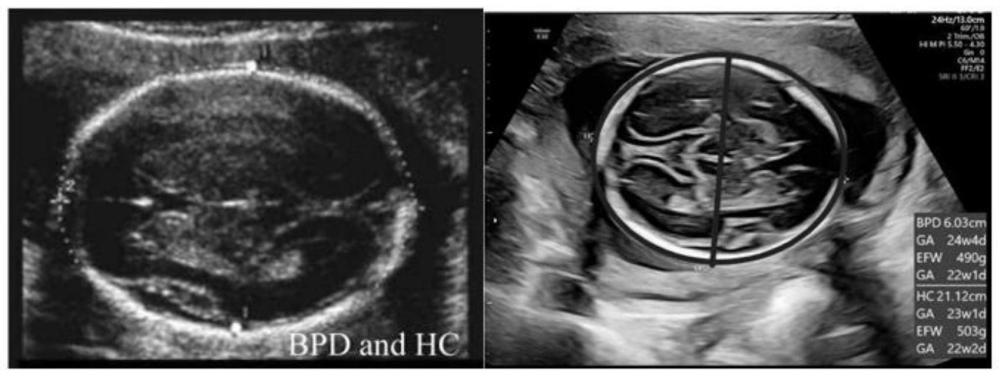

| 所属领域: | |||||

| 摘要: | 本发明公开了一种孕37‑42周预测足月新生儿出生体重的方法,包括以下步骤,S1:建立新生儿体重预测模型;所述新生儿体重预测模型为EFW=357.642×PC1‑121.302×PC2+3233.567,其中,PC1=0.688×XBPD+0.643×XHC+0.786×XAC+0.672×XHL+0.695×XFL+0.866×XTvol+0.809×XTmid+0.850×XAvol+0.808×XAmid;PC2=0.347×XBPD+0.466×XHC+0.097×XAC+0.423×XHL+0.471×XFL‑0.350×XTvol‑0.393×XTmid‑0.339×XAvol‑0.393×XAmid;S2:孕37‑42周胎儿二维超声参数测量;S3:孕37‑42周胎儿三维超声参数测量;S4:将步骤S2和S3中测量到的胎儿超声参数数据代入步骤S1中的新生儿体重预测模型中,计算求得新生儿的预测体重。该方法将胎儿二维超声数据和三维超声数据结合起来,能够提高足月新生儿出生体重预测的准确率。 | ||||